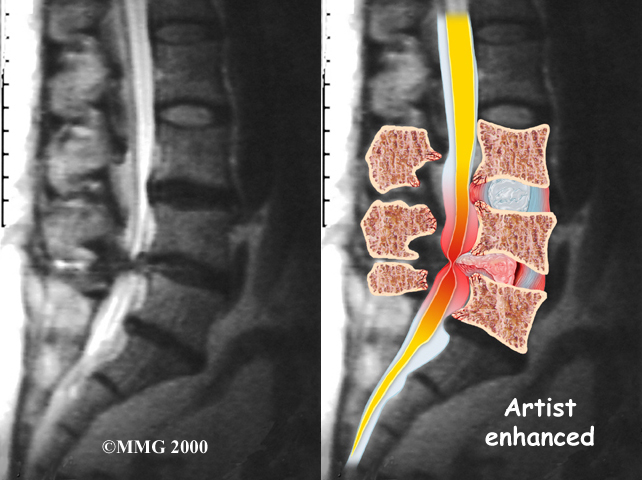

Your physician may first order X-rays to pinpoint the cause of your discomfort. X-rays can show if the problems are from changes in the bones of the spine. The images can show if degeneration has caused the space between the vertebrae to collapse. X-rays may also reveal any bone spurs sticking into the spinal canal.

The best way to see the effects and extent of lumbar spinal stenosis is with a (MRI) scan. The MRI machine uses magnetic waves rather than X-rays to show the soft tissues of the body. This test gives a clear picture of the spinal canal and whether the nerves inside are being squeezed. This machine creates pictures that look like slices of the area your doctor is interested in. The test does not require dye or a needle.

Computed tomography (a CT scan) may be ordered for those patients who can’t have an MRI for some reason, when the results of the MRI are unclear, or symptoms don’t match the MRI findings. The CT scan is a detailed X-ray that lets your doctor see slices of bone tissue. The image can show any bone spurs that may be sticking into the spinal column and taking up space around the spinal nerves.